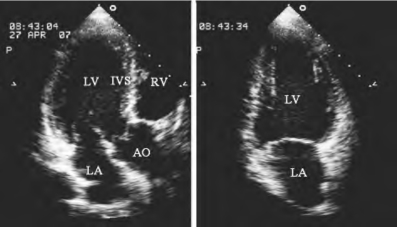

-